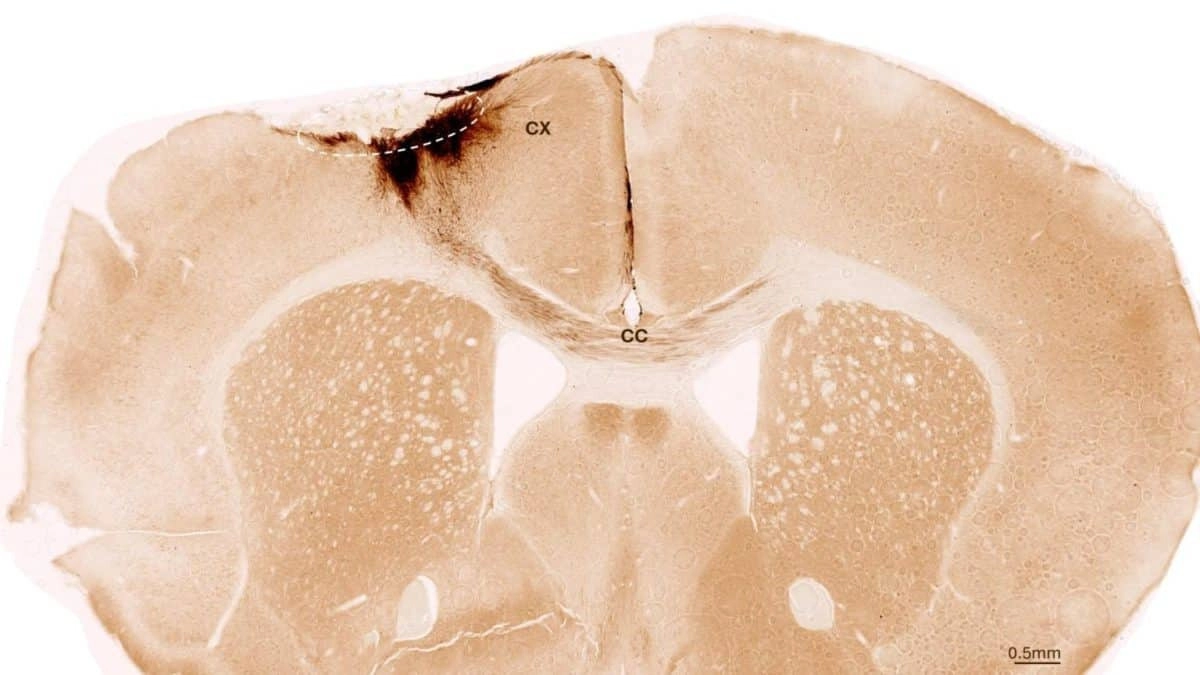

Корональный разрез мозга мыши после инсульта и трансплантации стволовых клеток / © University of Zurich

Исследователи вызвали у мышей перманентный инсульт, характеристики которого близки проявлению инсульта у человека. Животных генетически модифицировали, чтобы они не отторгали стволовые клетки человека.

Через неделю ученые трансплантировали стволовые клетки в поврежденную область мозга. Они следили за результатами, используя различные визуализирующие и биохимические методы. Исследователи обнаружили, что стволовые клетки выживали в течение всего периода наблюдения — пяти недель. Большинство из них превратились в нейроны, взаимодействующие с уже существующими клетками мозга.

Исследователи обнаружили и другие признаки регенерации: образовывались новые кровеносные сосуды, уменьшались воспалительные процессы и улучшалась целостность гематоэнцефалического барьера. Трансплантация стволовых клеток у мышей также обратила двигательные нарушения, вызванные инсультом.